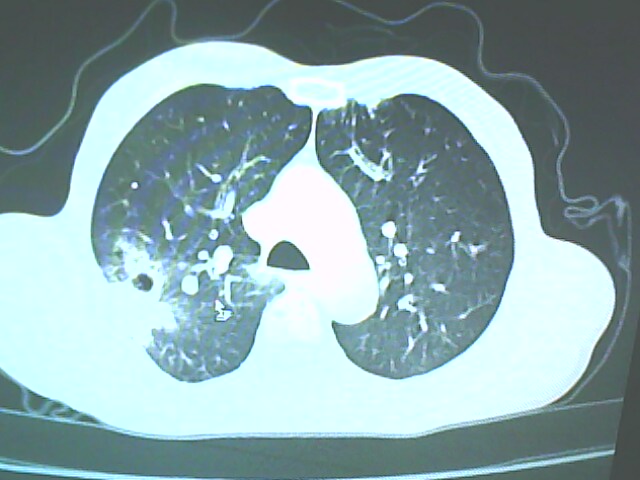

考虑癌性空洞可能性大,空洞内壁不规则,病灶周围模糊,分叶、有毛刺

考虑癌性空洞可能性大,空洞内壁不规则,病灶周围模糊,分叶、有毛刺。

空洞内壁不规则,病灶周围模糊,分叶、毛刺呈日光放射状,突然截断,支持考虑癌性空洞

从年龄及影像特征均支持癌性空洞。

考虑右肺上叶后段周围型肺癌并癌性空洞形成。

考虑癌性空洞可能性大,内壁不规则,洞壁薄厚不均呈结节状突起,边缘模糊,分叶,毛刺

典型癌性空洞(偏心性,壁厚薄不均,内壁不光整),周围毛刺较僵硬,且有刺突征和血管聚集征